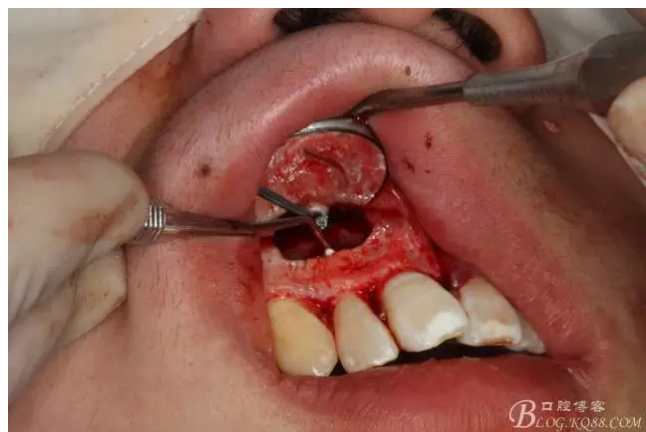

圖2.根管治療術(shù)后直接局部 麻醉下切開(kāi)、翻瓣,發(fā)現(xiàn)12唇側(cè)骨壁有綠豆大小骨缺損

圖3.依缺損部位為中心,逐漸去骨,完整暴露出囊壁。

圖4.摘除囊壁后形成的巨大骨腔

圖5.清理骨腔,可以看到12的根尖暴露在骨腔內(nèi)。